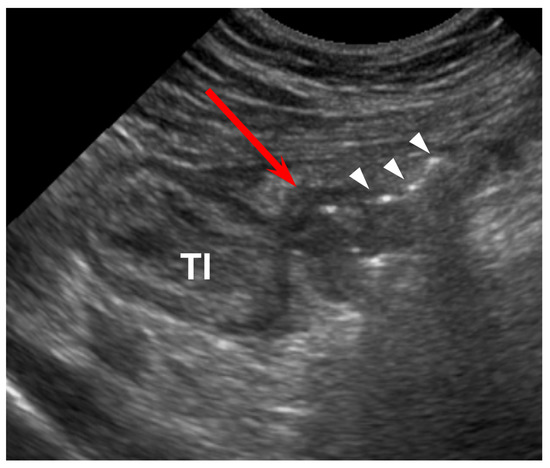

Figure 2. Sixty-seven-year-old male (patient #2) with acute perforated ileal diverticulitis. (A,B) Axial CT scans show ileal wall thickening (TI) with mesenteric abscess (A) and mesenteric fat infiltration. There is no definite inflamed diverticulum on CT. However, adjacent ileal diverticulum (arrowhead) supports the diagnosis of perforated ileal diverticulitis with abscess formation. (C) US scan with linear transducer reveals outpouching inflamed diverticulum (*) protruding from the terminal ileum (TI) and connecting to mesenteric abscess (A) with focal perforation site (arrow). (D) Barium study after 1 month shows two diverticula (arrowheads) protruding from the terminal ileum and multiple diverticula from the colon.

The CT findings for acute ileal diverticulitis are summarized in Table 2. All 17 patients had ileal diverticulum along the mesenteric border. Inflamed diverticulum was seen in 16 patients (94.1%) (Figure 1). The remaining patient did not have an inflamed diverticulum at the center of ileal wall thickening with abscess; however, adjacent ileal diverticula supported the diagnosis of acute ileal diverticulitis with perforation, and barium study after 1 month demonstrated two ileal diverticula along the mesenteric border (Figure 2). Three patients had radiodense fecalith within the inflamed diverticulum (Figure 3). All 17 patients had mesenteric fat infiltration with varying degrees and ileal wall thickening. Five patients (29.4%) were diagnosed with perforated ileal diverticulitis, which had the following findings: abscess (n = 2) (Figure 2), extraluminal fluid with air (n = 3) (Figure 4), and/or focal defect in the diverticular sac (n = 2) (Figure 5). Mesenteric venous gas (Figure 4) and mesenteric venous thrombosis were seen in two patients (11.8%), respectively.

The US findings for acute ileal diverticulitis are summarized in Table 3. All patients showed outpouching inflamed diverticular sac connecting to the ileum, peridiverticular inflamed fat presenting as hyperechoic fat around the diverticulum, and increased color flow to the diverticulum and surrounding inflamed fat on CDI (Figure 1). The inflamed diverticulum exhibited variable echogenicity (Figure 2 and Figure 3). Like CT findings, eight patients had a single diverticulum and nine patients had multiple diverticula. Unlike CT, US examinations diagnosed perforated ileal diverticulitis in seven patients. The findings indicated that five patients had both abscess and extraluminal air bubble (Figure 4 and Figure 5), one patient had only extraluminal air bubble (Figure 6), and one patient had only abscess.

Historically, acute ileal diverticulitis has been diagnosed on exploratory laparotomy for other challenging differential diagnoses [1,20]. The technological advances and widespread use of CT have enabled radiologists to play an essential role in diagnosing acute ileal diverticulitis [3,16,18]. The characteristic CT findings of acute ileal diverticulitis in this study included ileal wall thickening with small-sized inflamed diverticulum at the mesenteric side and surrounding mesenteric fat infiltration, which was consistent with CT findings in previous studies [3,4,5,6,7,8,9,10,11,13,16,18,24,30]. Especially, direct visualization of the inflamed diverticulum was the key feature in diagnosing acute ileal diverticulitis. Sixteen of 17 patients had direct visualization of inflamed diverticulum on CT. The remaining patient, who was diagnosed with perforated diverticulitis with abscess, did not show an inflamed diverticulum on CT. However, US demonstrated inflamed diverticulum protruding from the ileum and connecting with the abscess in the patient. We believe that US could play a complementary role if the inflamed diverticulum was not seen on CT.